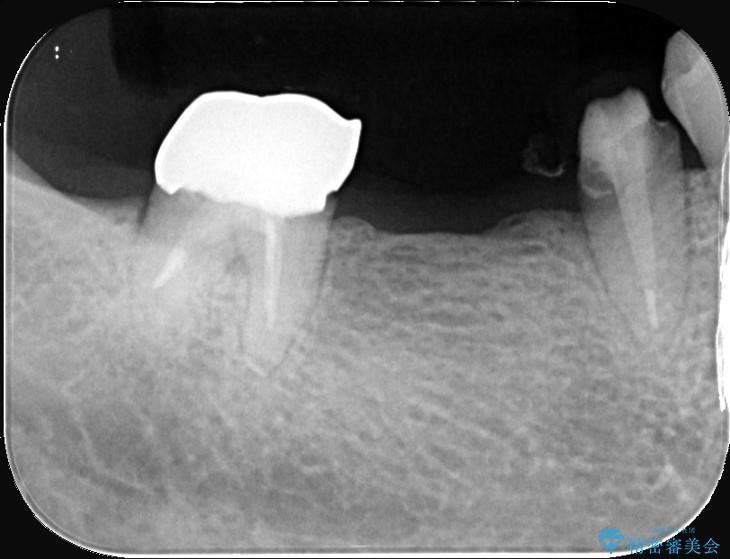

セラミックに比べ、破折リスクの少ない金属を使用したブリッジでのやり替えとなりました。

両支台歯が失活歯のため、どちらかもしくは両方の歯が破折した際、再度ブリッジを除去した治療が必要になるリスクとインプラント治療のご提案もさせていただきましたが、ブリッジでの治療を希望されました。

右下5番は支台歯CR築造を行っています。